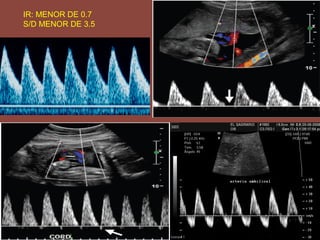

IR: MENOR DE 0.7

S/D MENOR DE 3.5

IR: MENOR DE0.7 S/D MENOR DE 3.5

FLUJOMETRIA NORMAL ALA SEMANA 7 A 10-13

ANORMALIDADES DEL CORDONUMBILICAL (NUDO) PICO SISTOLICO VELOCIDAD DE FIN DE DIASTOLE